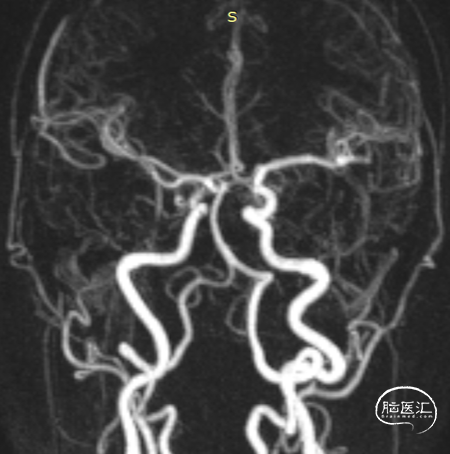

术后6个月造影随访提示动脉瘤完全愈合,载瘤动脉通畅。

4、该病例即刻造影显示血流重构满意,瘤腔内血流明显淤滞。术后六个月及12个月随访,均显示动脉瘤愈合,载瘤动脉通畅无狭窄。